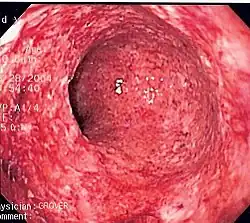

![]() Endoskopowy obraz zapalenia jelita w chorobie Crohna ukazujący głębokie owrzodzenie | |

| Endoskopia | Głębokie geograficzne owrzodzenia | Ciągłe owrzodzenia |